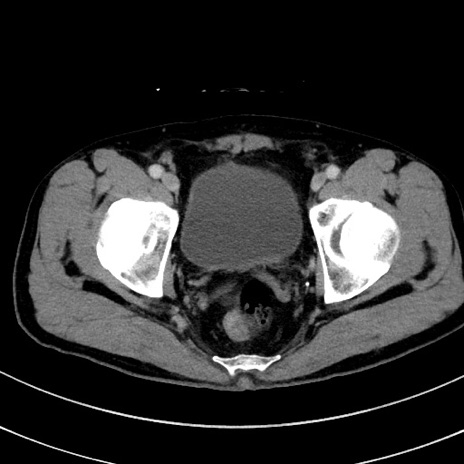

症例8(横断像)

【症例】 60歳代男性

【主訴】 黒色吐物

【現病歴】 4日前から嘔気自覚、2日前の朝食後にも嘔気あり、自分で手で嘔吐反射起こし嘔吐したところ血が混ざっていたため受診。

【既往歴】 5年前汎発性腹膜炎を伴う急性虫垂炎で手術、高血圧、前立腺肥大症、高脂血症

【身体所見】 腹部正中に手術癩痕あり 腹部平坦・軟圧痛なし膨満感あり

【データ】WBC 8400、CRP 4.54